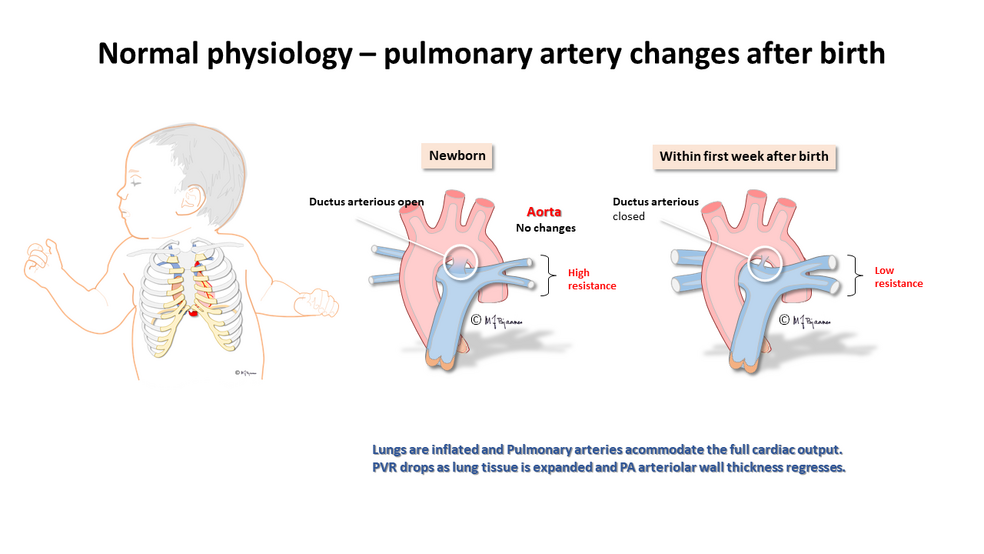

PDA Pathophysiology and Anatomy

What is this PDA and why do the doctors want to close it

Patent Ductus Arteriosus PDA in the newborn

PDA in Preterm Infants Neonatal Network South East

25 PDA in preterm infants 75 PATENT DUCTUS ARTERIOSUS IN PRETERM